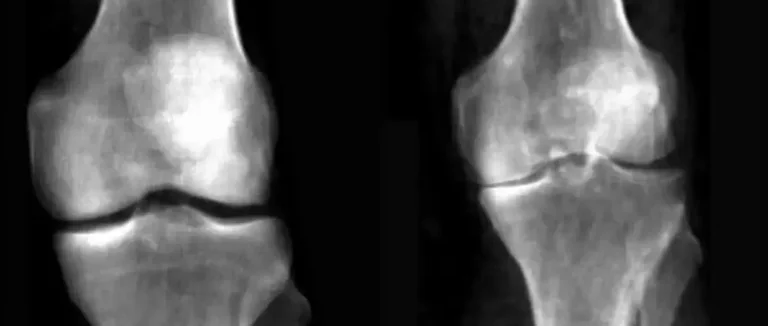

Diagnostic de l'Arthrite et des Maladies Inflammatoires

La scintigraphie osseuse nucléaire est un outil essentiel pour diagnostiquer l'arthrite et les maladies inflammatoires. Elle permet de voir les modèles de distribution de l'activité osseuse anormale. Cela aide à identifier les types d'arthrite et à connaître leur étendue.

Modèles de distribution caractéristiques

L'arthrite se montre par des modèles de distribution spécifiques sur les images de scintigraphie. Les zones d'absorption accrue du traceur radioactif montrent une activité osseuse anormale. Cela peut être lié à différentes formes d'arthrite, comme l'arthrose qui augmente l'absorption dans les articulations touchées.

Les images de la scintigraphie montrent clairement les différences entre les types d'arthrite. La polyarthrite rhumatoïde, par exemple, montre une activité anormale symétrique dans les mains et les pieds.

Différenciation entre types d'arthrite

La scintigraphie osseuse nucléaire aide à distinguer les types d'arthrite par leurs modèles de distribution. Cette distinction est essentielle pour un diagnostic précis et un traitement adapté.

● L'arthrose se caractérise par une absorption accrue dans les articulations touchées.

● La polyarthrite rhumatoïde présente souvent une distribution symétrique de l'activité anormale.

● Les arthrites séropositives montrent des modèles distincts qui aident à les identifier.